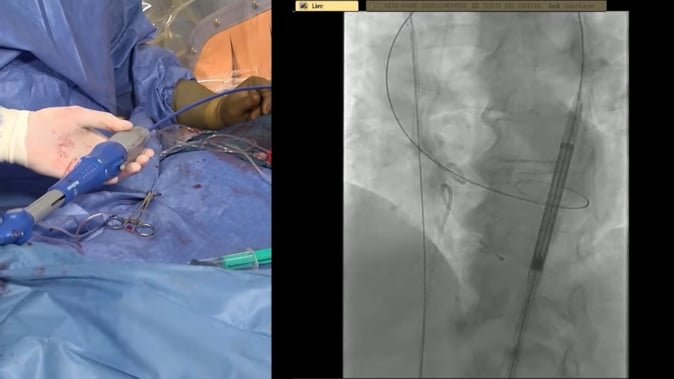

TAVI procedure optimisation with the cusp overlap technique

27 Sep 2021 – From PCR Tokyo Valves 2021

In this session, the speakers present the advantages of the cusp overlap technique, providing a technical overview, and predicting that it will lead to best-in-class permanent pacemaker implantation rates, and will also have a great impact on paravalvular leak rates and other clinical endpoints. They further support their point by...

TAVI implantation optimisation – Practical aspects of cusp overlap technique

Watch this session if you want to learn more about the contemporary cusp overlap implantation technique and to understand the practical aspects of how the cusp overlap technique can increase procedural predictability and reduce PPI rates.